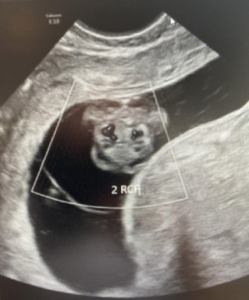

The ultrasound images demonstrated a single spinal column, two stomachs, and two hearts (Figure 2A). Two fused abdomens were observed, along with subcutaneous edema measuring 2.0 mm and 2.1 mm (Figure 2B). In addition, two pairs of moving legs were identified (Figure 2C). The trophoblast was located anteriorly, and a single corpus luteum was observed in the left ovary. Two follow-up examinations were required at 9 and 10 weeks of gestation to establish the diagnosis. At 9 weeks of gestation, the 3D ultrasound images lacked sufficient clarity for a definitive diagnosis (Figure 3). At 10 weeks of gestation, color Doppler imaging demonstrated two distinct cardiac activities, indicating the presence of two separate circulatory systems (Figure 4A). Three-dimensional imaging further revealed the face of one of the conjoined twins and confirmed the presence of two umbilical cords (Figure 4B).